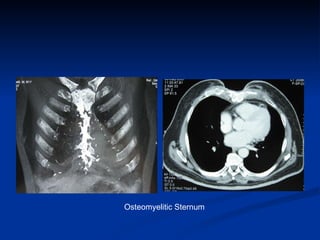

Osteomyelitic Sternum

How to make an early diagnosis The  Classic symptoms  and signs of acute infection are  infrequently  encountered   Fever and Leukocytosis  in the absence of local symptoms or signs may be the only presenting clinical features in a small percentage of patients  Wound discharge  is the most common presentation and occurs in 70% to 90%  Local symptoms include wound pain, tenderness, and sternal instability  Chest roentgenograms  are rarely helpful in the early diagnosis  Chest computed tomography scanning with mediastinal aspiration